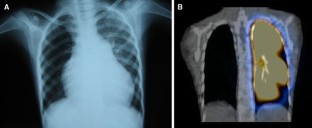

Takayasu’s Arteritis Mimicking Unilateral Pulmonary Artery Agenesis in a Child With Severe Pulmonary Hypertension and Right Heart Failure: A Diagnostic Dilemma

Affliction of the pulmonary arteries in Takayasu’s arteritis is uncommon. Moreover the incidence of pulmonary artery involvement in this condition is often underestimated because of asymptomatic nature in most patients. Severe involvement may however present with pulmonary artery hypertension and hemoptysis, which may prove to be fatal. This case report describes a 9-year-old girl with severe pulmonary hypertension and right heart failure secondary to total occlusion of the right pulmonary artery. Detailed clinical examination and computed tomography (CT) angiography confirmed this diagnosis.

Fig. 2